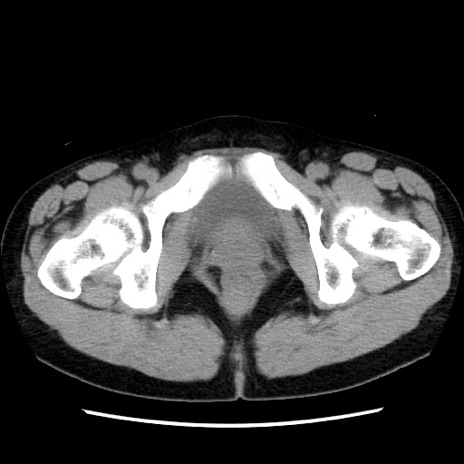

症例10(横断像)

【症例】 50歳代女性

【主訴】 腹痛

【現病歴】前日生レバーを食べた。今朝に排便あり。 昼前に突然発症の腹痛を生じ、当院救急外来を受診した。

【既往歴】 子宮筋腫にてで子宮全摘後

【身体所見】 意識清明、腹部:平坦、軟、下腹部やや左を中心に圧痛・反跳痛あり、筋性防御あり

【データ】WBC 7800、CRP 0.07